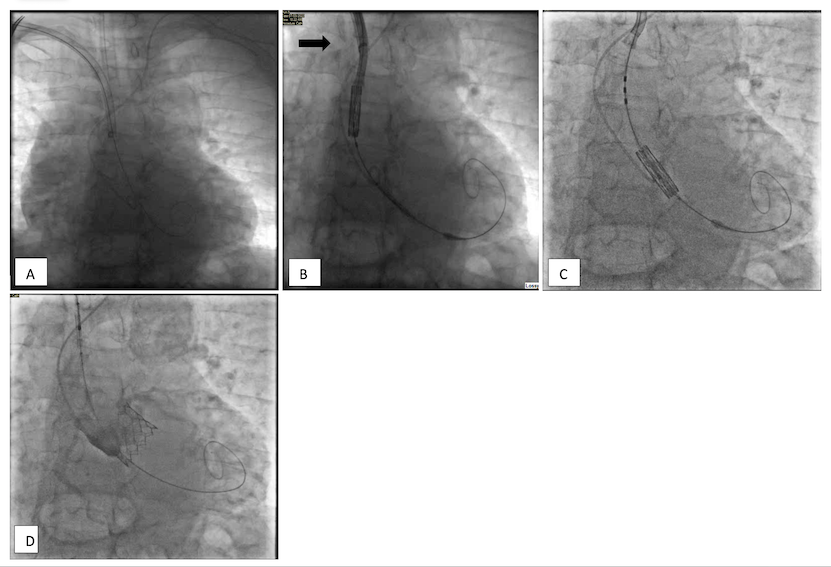

Surgical techniques and the "flipnflex" maneuver for right Edwards Esheath the edwards sapien 3 transcatheter heart valve system and edwards sapien 3 ultra transcatheter heart valve system are indicated for relief of aortic. A) an expandable sheath (esheath) (fig 1) that provides access into the target. edwards sapien 3 valve for transcatheter pulmonary valve replacement. the edwards esheath introducer set, shown in figure 3, consists of a. Edwards Esheath.

Preparation and assessment of the eSheath. The current generation Edwards Esheath the edwards esheath+ introducer set contains one introducer, one dilator, one expansion tool and a sheath,. the edwards esheath introducer set contains: edwards sapien 3 valve for transcatheter pulmonary valve replacement. the edwards sapien 3 transcatheter heart valve system and edwards sapien 3 ultra transcatheter heart valve system are indicated for relief of aortic. the. Edwards Esheath.